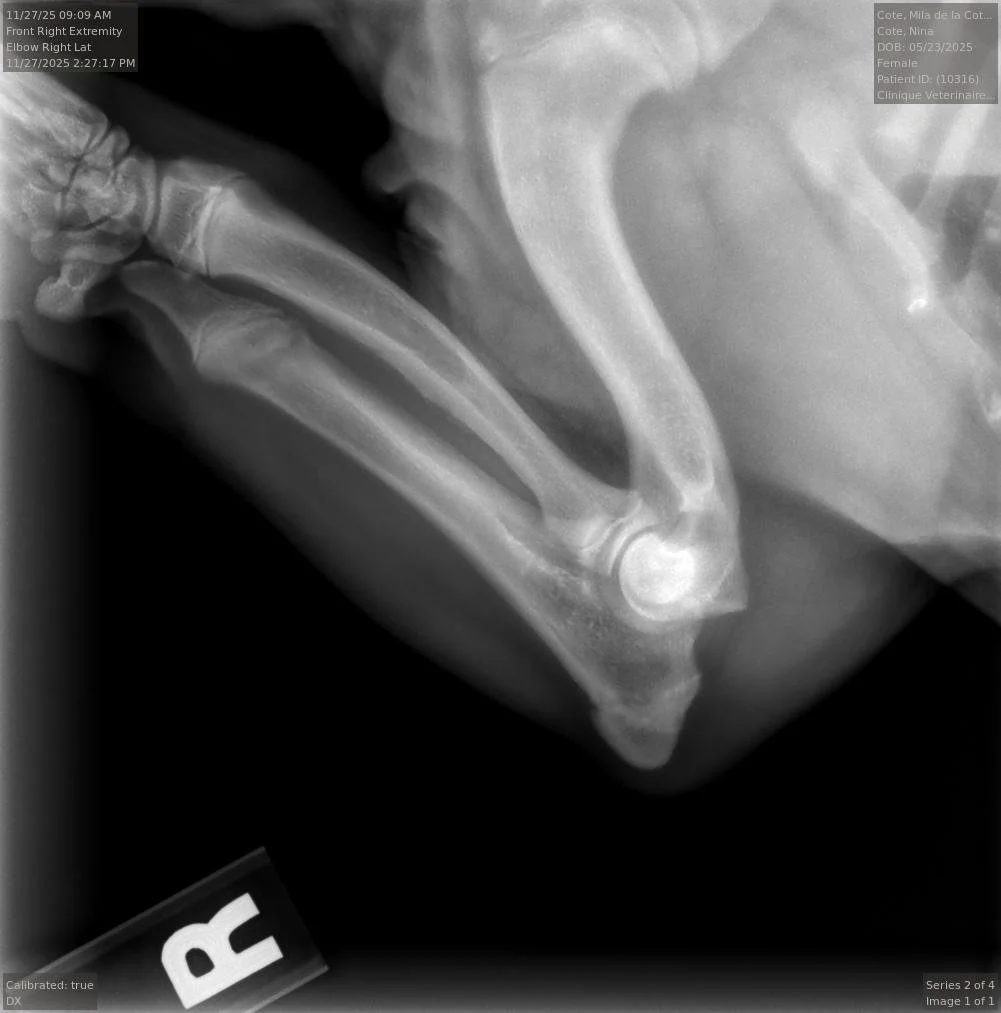

Nous commencerons les tests OFA de la race dès l'âge de 6 mois.